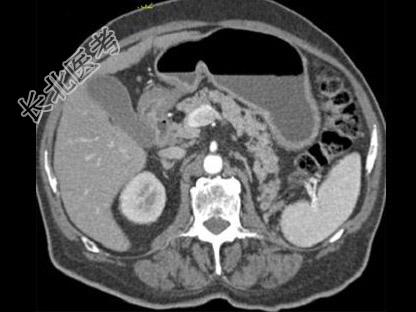

- 单项选择题根据所提供的图像,最可能的诊断是 ( )

A、胰腺脂肪瘤

B、正常胰腺

C、胰腺癌

D、胰腺转移癌

E、以上都不是